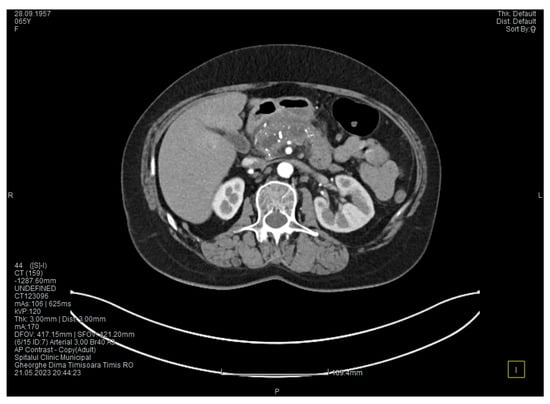

Contrast-enhanced computed tomography highlighted signs of chronic pancreatitis with multiple calcifications throughout the pancreatic parenchyma, calcareous conglomerates in the cephalic area (Figure 5), dilatation of the Wirsung duct measuring approximately 15 mm, a cephalo-uncinate pseudocyst measuring 30/31/32 mm (Figure 6), and densification of the pericephalic pancreatic fat; all the changes were more pronounced compared to the previous examinations. Other findings included acute cholecystitis with thickening of the gallbladder wall and iodophilia of the mucosa, small dilatations of the intrahepatic bile ducts, fluid accumulation in the hepatic hilum and in the periduodenal area, inflammatory wall thickening in the gastric antro-pyloric region and in the duodenum (I, II), and inflammatory lymph nodes in the peripancreatic area and in the hepatic hilum measuring up to 11 mm.

The CT scan showed that the pancreatic changes evolved, with an increase in the cephalic cyst and in the diameter of the pancreatic and biliary ducts. These findings suggested the diagnosis of groove pancreatitis since the changes in the pancreas were localized in the head and are extended towards the duodenum; however, this disease is quite rare in women [5]. Since most authors consider that the endoscopic retrograde cholangiopancreatography is challenging and potentially risky, and because in our case the endoscopy was technically difficult due to the local changes, we decided to perform cephalic duodenopancreatectomy, a surgical procedure recommended by most authors.

Figure 5. CT scan at the fourth episode of acute pancreatitis shows calcifications in the pancreatic head, thickening of the duodenal wall, and partial occlusion of the duodenum.

Figure 6. CT scan at the fourth episode of acute pancreatitis shows a slightly increased cyst and calcifications in the pancreatic head.